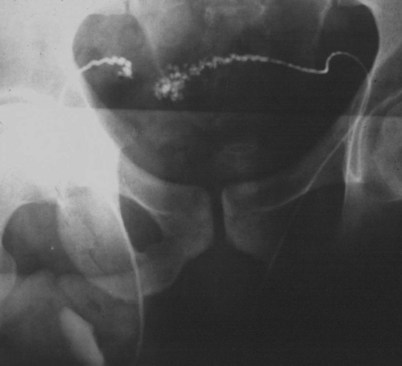

If a large amount of fluid is found in the vasal lumen and microscopic examination reveals the presence of sperm, the obstruction is toward the seminal vesicle end of the vas. In these cases the vas is usually markedly dilated. A 2-0 Proline suture can be passed toward the seminal vesicle end of the vas and a clamp placed on the Proline when the suture passes no farther. This is particularly useful for delineating the site of inguinal obstruction from prior groin surgery. If the obstruction is proximal to the inguinal scar, formal vasography is performed by passing a No. 3 whistle-tip ureteral catheter toward the seminal vesicle end of the vas. A 16-Fr Foley catheter is placed in the bladder, and the balloon is filled with 5 mL of air. Placing the balloon on gentle traction before vasography prevents reflux of contrast into the bladder, which can obscure detail (Fig. 22–5). The air-filled balloon also identifies the location of the bladder neck relative to any obstruction. After the vasa have been cannulated, vasograms are performed with the injection of 0.5 mL of water-soluble contrast media (Fig. 22–6). If vasography reveals obstruction at the site of the ejaculatory ducts (Fig. 22–7), indigo carmine is injected in both vasa to assist a transurethral resection (TUR) of the ejaculatory ducts (see Diagnosis later). If both vasa are visualized after injection of contrast into only one vas (Fig. 22–8), it means both vasa empty into a single cavity, usually a midline ejaculatory duct cyst.

Figure 22–5 Placing the balloon on gentle traction before vasography prevents reflux of contrast into the bladder, which can obscure detail.